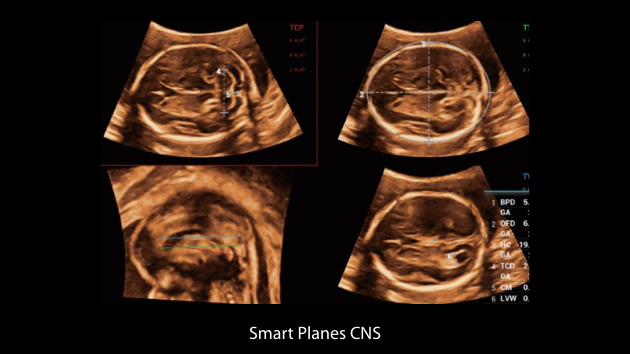

Nuewa I9, kad?nlara ve yenido?anlara y?nelik sa?l?k hizmetleri i?in ?zel olarak tasarlam??t?r ve i?ten d??a yenilik?i bir deneyim sunmaktad?r. Bu yenilikler, karma??k klinik senaryolara ili?kin derinlemesine bilgilere dayal? olarak geli?tirilmi?tir ayr?ca do?ru ve zaman?nda yan?tlar?n yan? s?ra, ola?an├╝st├╝ verimlilik ve ola?an├╝st├╝ kullan?c? deneyimi sunar.